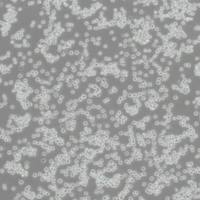

| 生长特性 | 悬浮细胞 |

| 细胞形态 | 淋巴细胞样 |